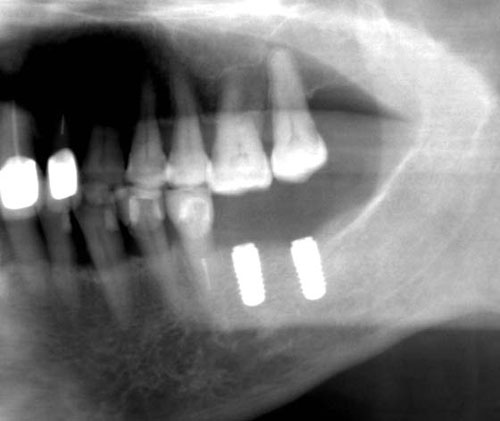

近期,泰安市中心医院口腔科引进了国际先进的口腔种植系统,成立了“口腔种植中心”,并为4位患者成攻实施了牙种植手术(其中两位患者采取拔牙后即可植骨、即可种植),取得了令人满意的效果。

大众网泰安讯(通讯员 于肖鹏)近期,泰安市中心医院口腔科引进了国际先进的口腔种植系统,成立了“口腔种植中心”,并为4位患者成攻实施了牙种植手术(其中两位患者采取拔牙后即可植骨、即可种植),取得了令人满意的效果。

所谓“种植牙”,是指将类似牙根的种植体植入牙槽骨,待其愈合后再在其上面修复缺失牙。因种植牙不仅牙根稳固,能和真牙一样咀嚼食物,而且牙冠美观,被称为“人类的第三副牙齿”。种植牙有如下优点:⑴ 种植牙外形逼真、稳固、舒适、卫生、咀嚼功能恢复好;⑵人工种植牙不采用磨削相邻真牙的方法来固定假牙,因而不损伤邻牙;⑶无论是单个牙、多个牙缺失,还是全口牙缺失都可采用种植的方法来治疗;⑷根据不同情况,种植手术可以选择在拔牙后即刻手术,也可以延期手术;⑸手术是在局麻下进行,术中和术后不会有明显的疼痛,无需住院,一般也不影响正常工作。

种植牙由于其美观、舒适、耐用与真牙相类似,深受患者欢迎,种植牙已经发展成为一门新兴学科即口腔种植学,种植牙技术已十分成熟。目前种植牙10年的存活率高达97.43%,世界上种植牙存留最长时间长达40多年。口腔种植技术的成功和发展,不仅完善了传统牙齿修复技术的不足,而且在功能与美观上给了人们崭新体验。只要能接受常规拔牙手术的缺牙患者,都可以考虑种植牙修复,种植义齿也并不为年龄所限。种植牙手术采用局部麻醉,创伤小。由于选用的是与人体相容性极好的生物材料,种植牙对人体不产生任何不良的副作用。